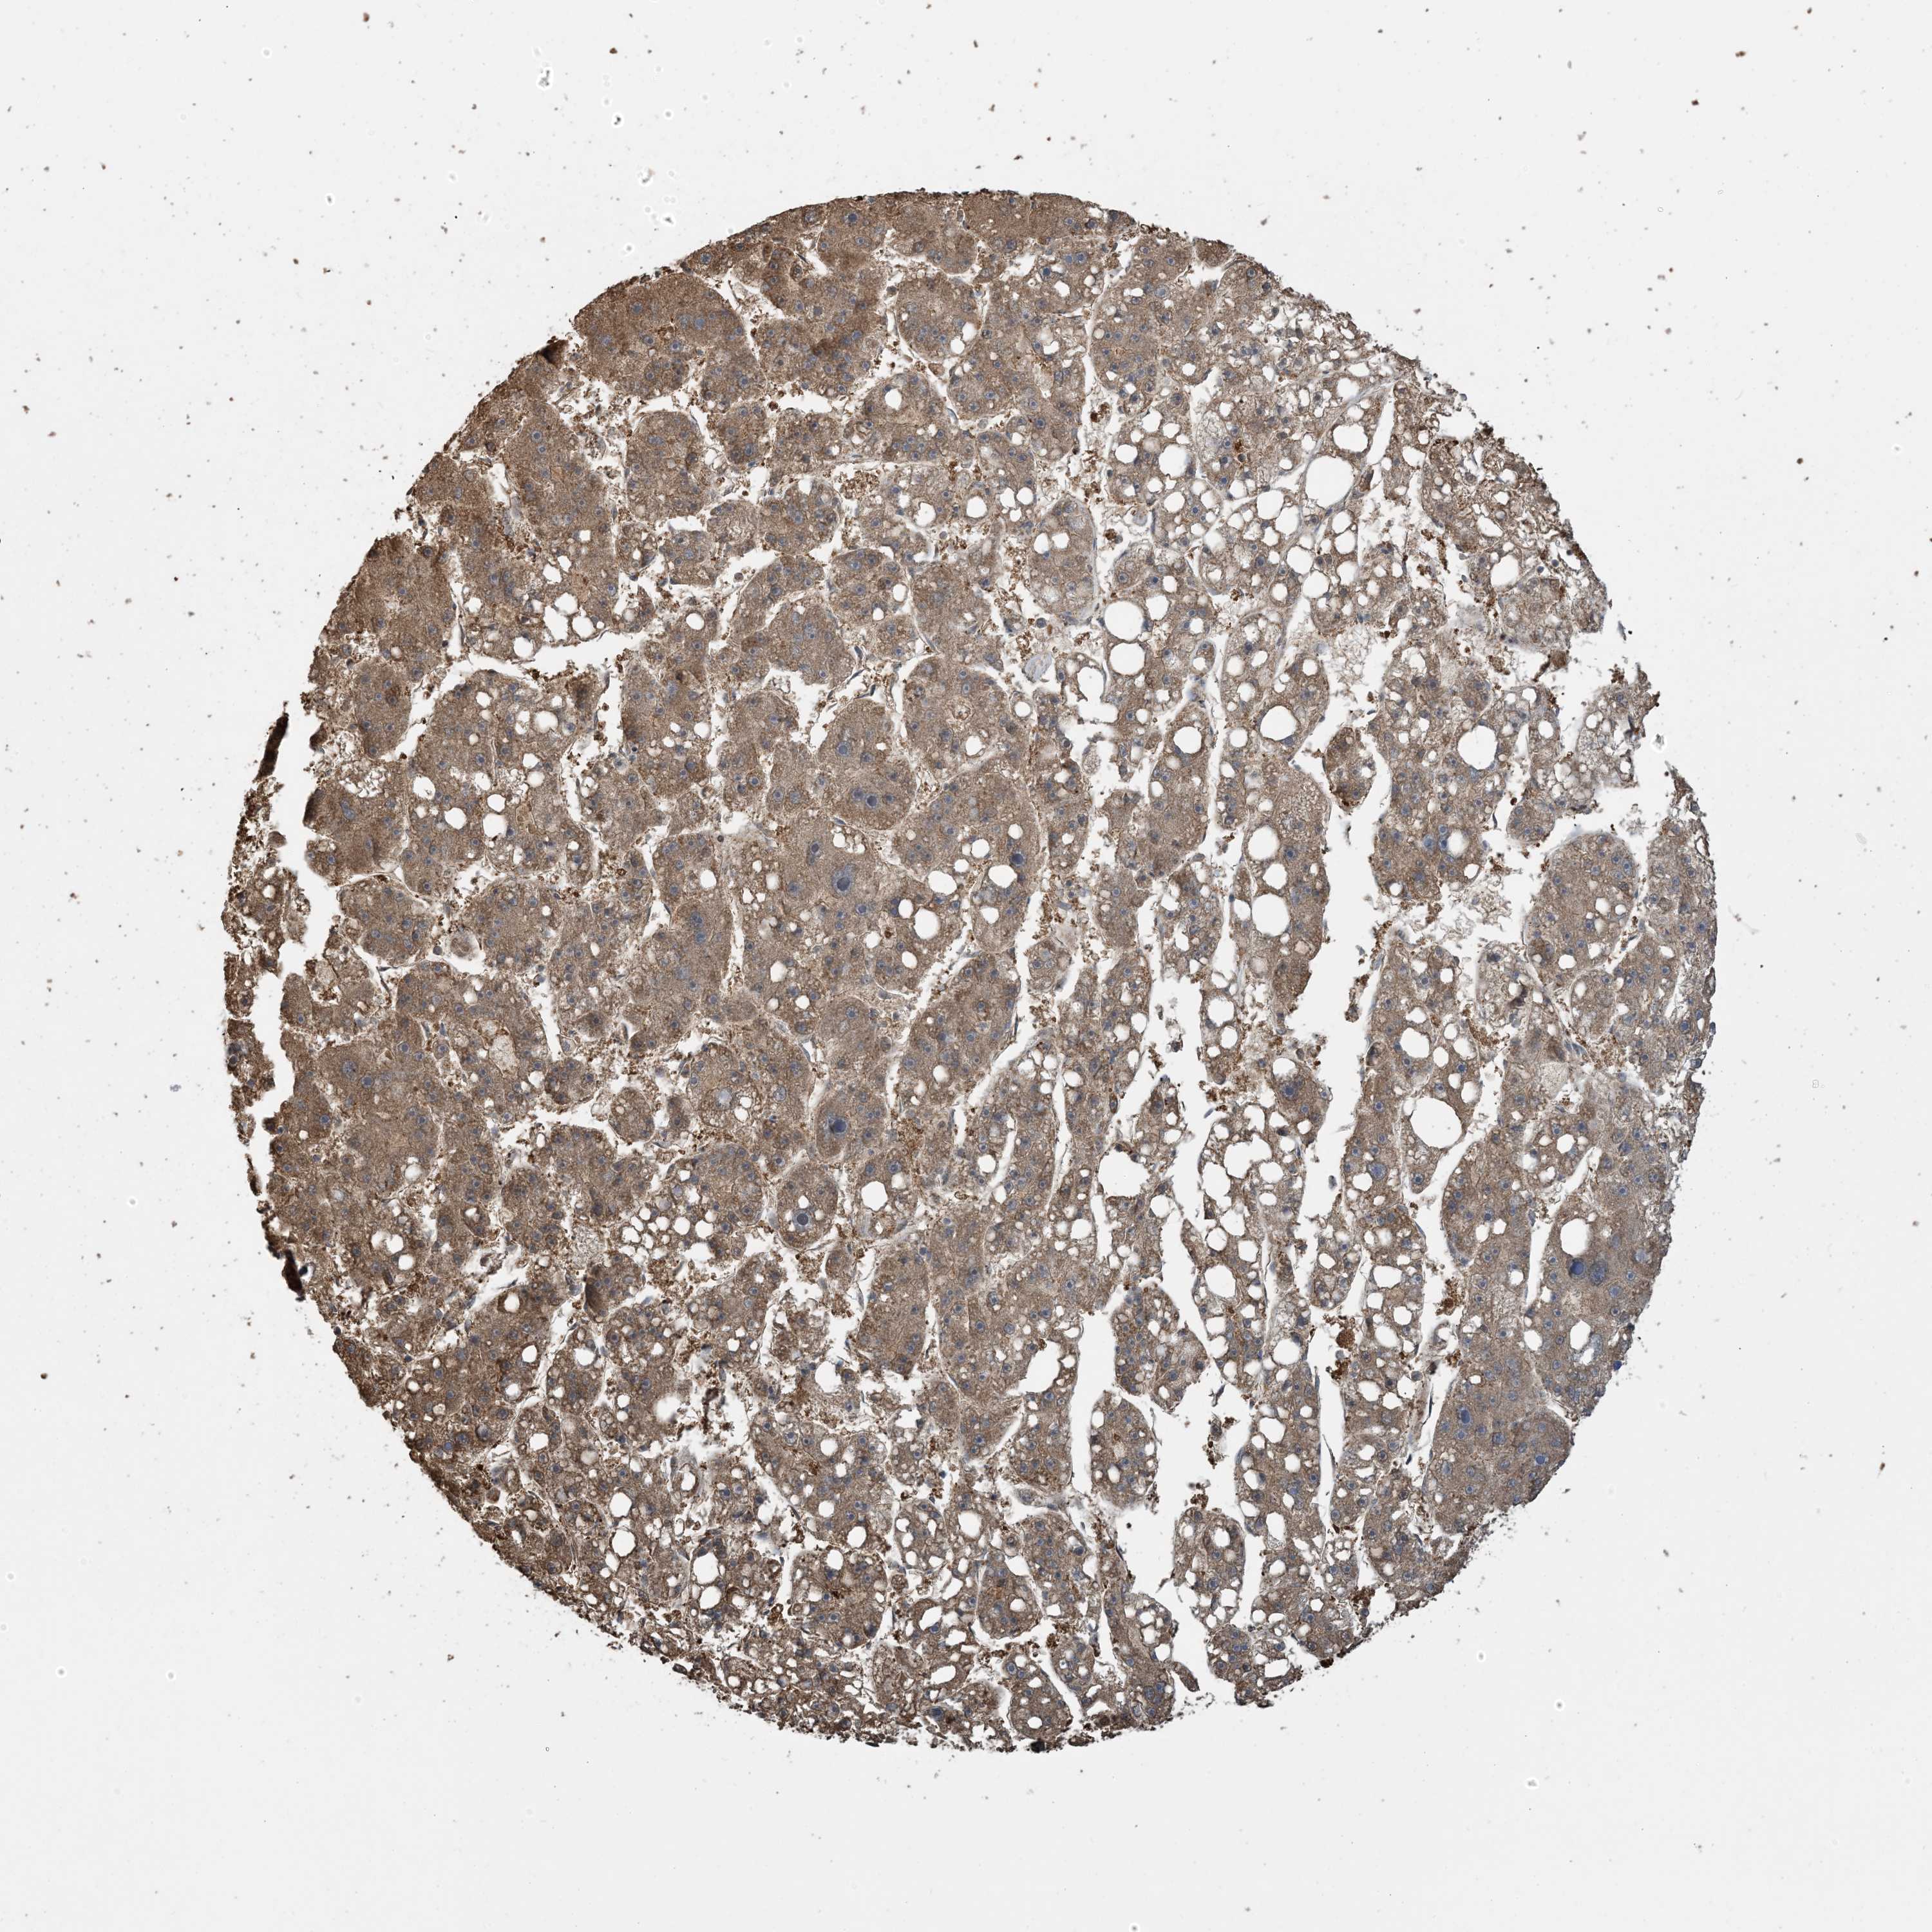

LIVER CANCER - Protein expressioni

A mouse-over function shows sample information and annotation data. Click on an image to view it in a full screen mode. Samples can be filtered based on level of antibody staining by selecting one or several of the following categories: high, medium, low and not detected. The assay and annotation is described here.

Note that samples used for immunohistochemistry by the Human Protein Atlas do not correspond to samples in the TCGA dataset.

Antibody stainingi

Antibody staining in the annotated cell types in the current human tissue is reported as not detected, low, medium, or high, based on conventional immunohistochemistry profiling in selected tissues. This score is based on the combination of the staining intensity and fraction of stained cells.

Each image is clickable and will lead to virtual microscopy that enables deeper exploration of all samples and also displays staining intensity scores, fraction scores and subcellular localization as well as patient and tissue information for each sample.

Antibody HPA052504

Antibody CAB017451

Antibody CAB032815

Staining

High

Medium

Low

Not detected

Intensity

Strong

Moderate

Weak

Negative

Quantity

>75%

75%-25%

<25%

None

Location

Nuclear

Cytoplasmic/membranous

Cytoplasmic/membranous,nuclear

Cholangiocarcinoma

Carcinoma, Hepatocellular, NOS